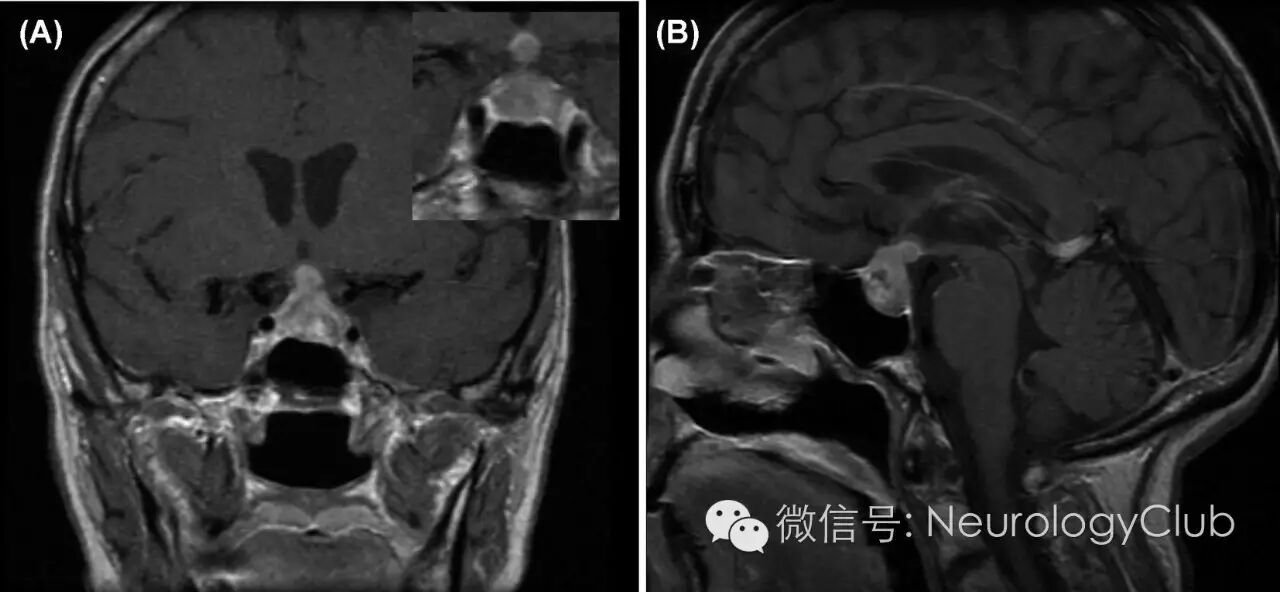

63岁女性,既往有抑郁症,子宫肌瘤,乳房纤维囊性变和抽烟史,表现为进行性间断性严重头痛和嗜睡伴视物模糊和周边视觉缺失。查体发现患者双颞侧偏盲,并经Humphrey视野检测证实(图1),右眼和左眼的视敏度(Snellen视力表)分别为6/6和6/7.5,而Ishihara色盲测试分别为7/13和3/13。瞳孔等大,对光反射灵敏,无相对性瞳孔传入障碍。眼底检查提示视盘苍白,左侧更为突出,但光学相干断层成像术未发现明显的视网膜神经纤维层变薄。颅神经和感觉运动功能未见异常。内分泌相关检测提示全面性垂体功能减退,并需要药物治疗尿崩症。患者头颅MRI检查发现鞍区肿块延伸至鞍上区压迫视交叉(图2)。后行病灶活检(图3)。

(图2:T1增强MRI提示不均匀强化的鞍区肿块延伸至鞍上池,毗邻并压迫视交叉。另可见稍低强化的坏死中心在病灶左侧下方

MRI是明确垂体肿瘤大小和部位的重要诊断工具,但影像上很难将鞍区转移瘤与其他肿瘤类型区分开来。本例MRI表现不典型,因肿瘤相对较小且累及垂体柄。其他有助于鉴别垂体大腺瘤和转移瘤的特征包括,前者边界不规则,可有硬脑膜增厚,骨质破坏和侵袭而非鞍区结构重建。垂体后叶T1高信号见于正常人,如果这一影像学表现消失可能提示肿瘤浸润漏斗部和垂体后叶。